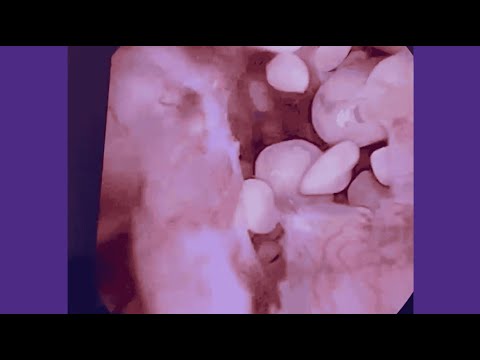

Ureteroscopy

Your physician can insert a small scope to view and remove smaller stones in the ureter or kidney. How they remove the stone will depend on the size of the stone. They will remove smaller stones with a basket. They will use a laser to break up a stone that is too large to remove with a basket. This is an outpatient surgical procedure with a short recovery time. Your physician may also insert a ureteral stent during this procedure.